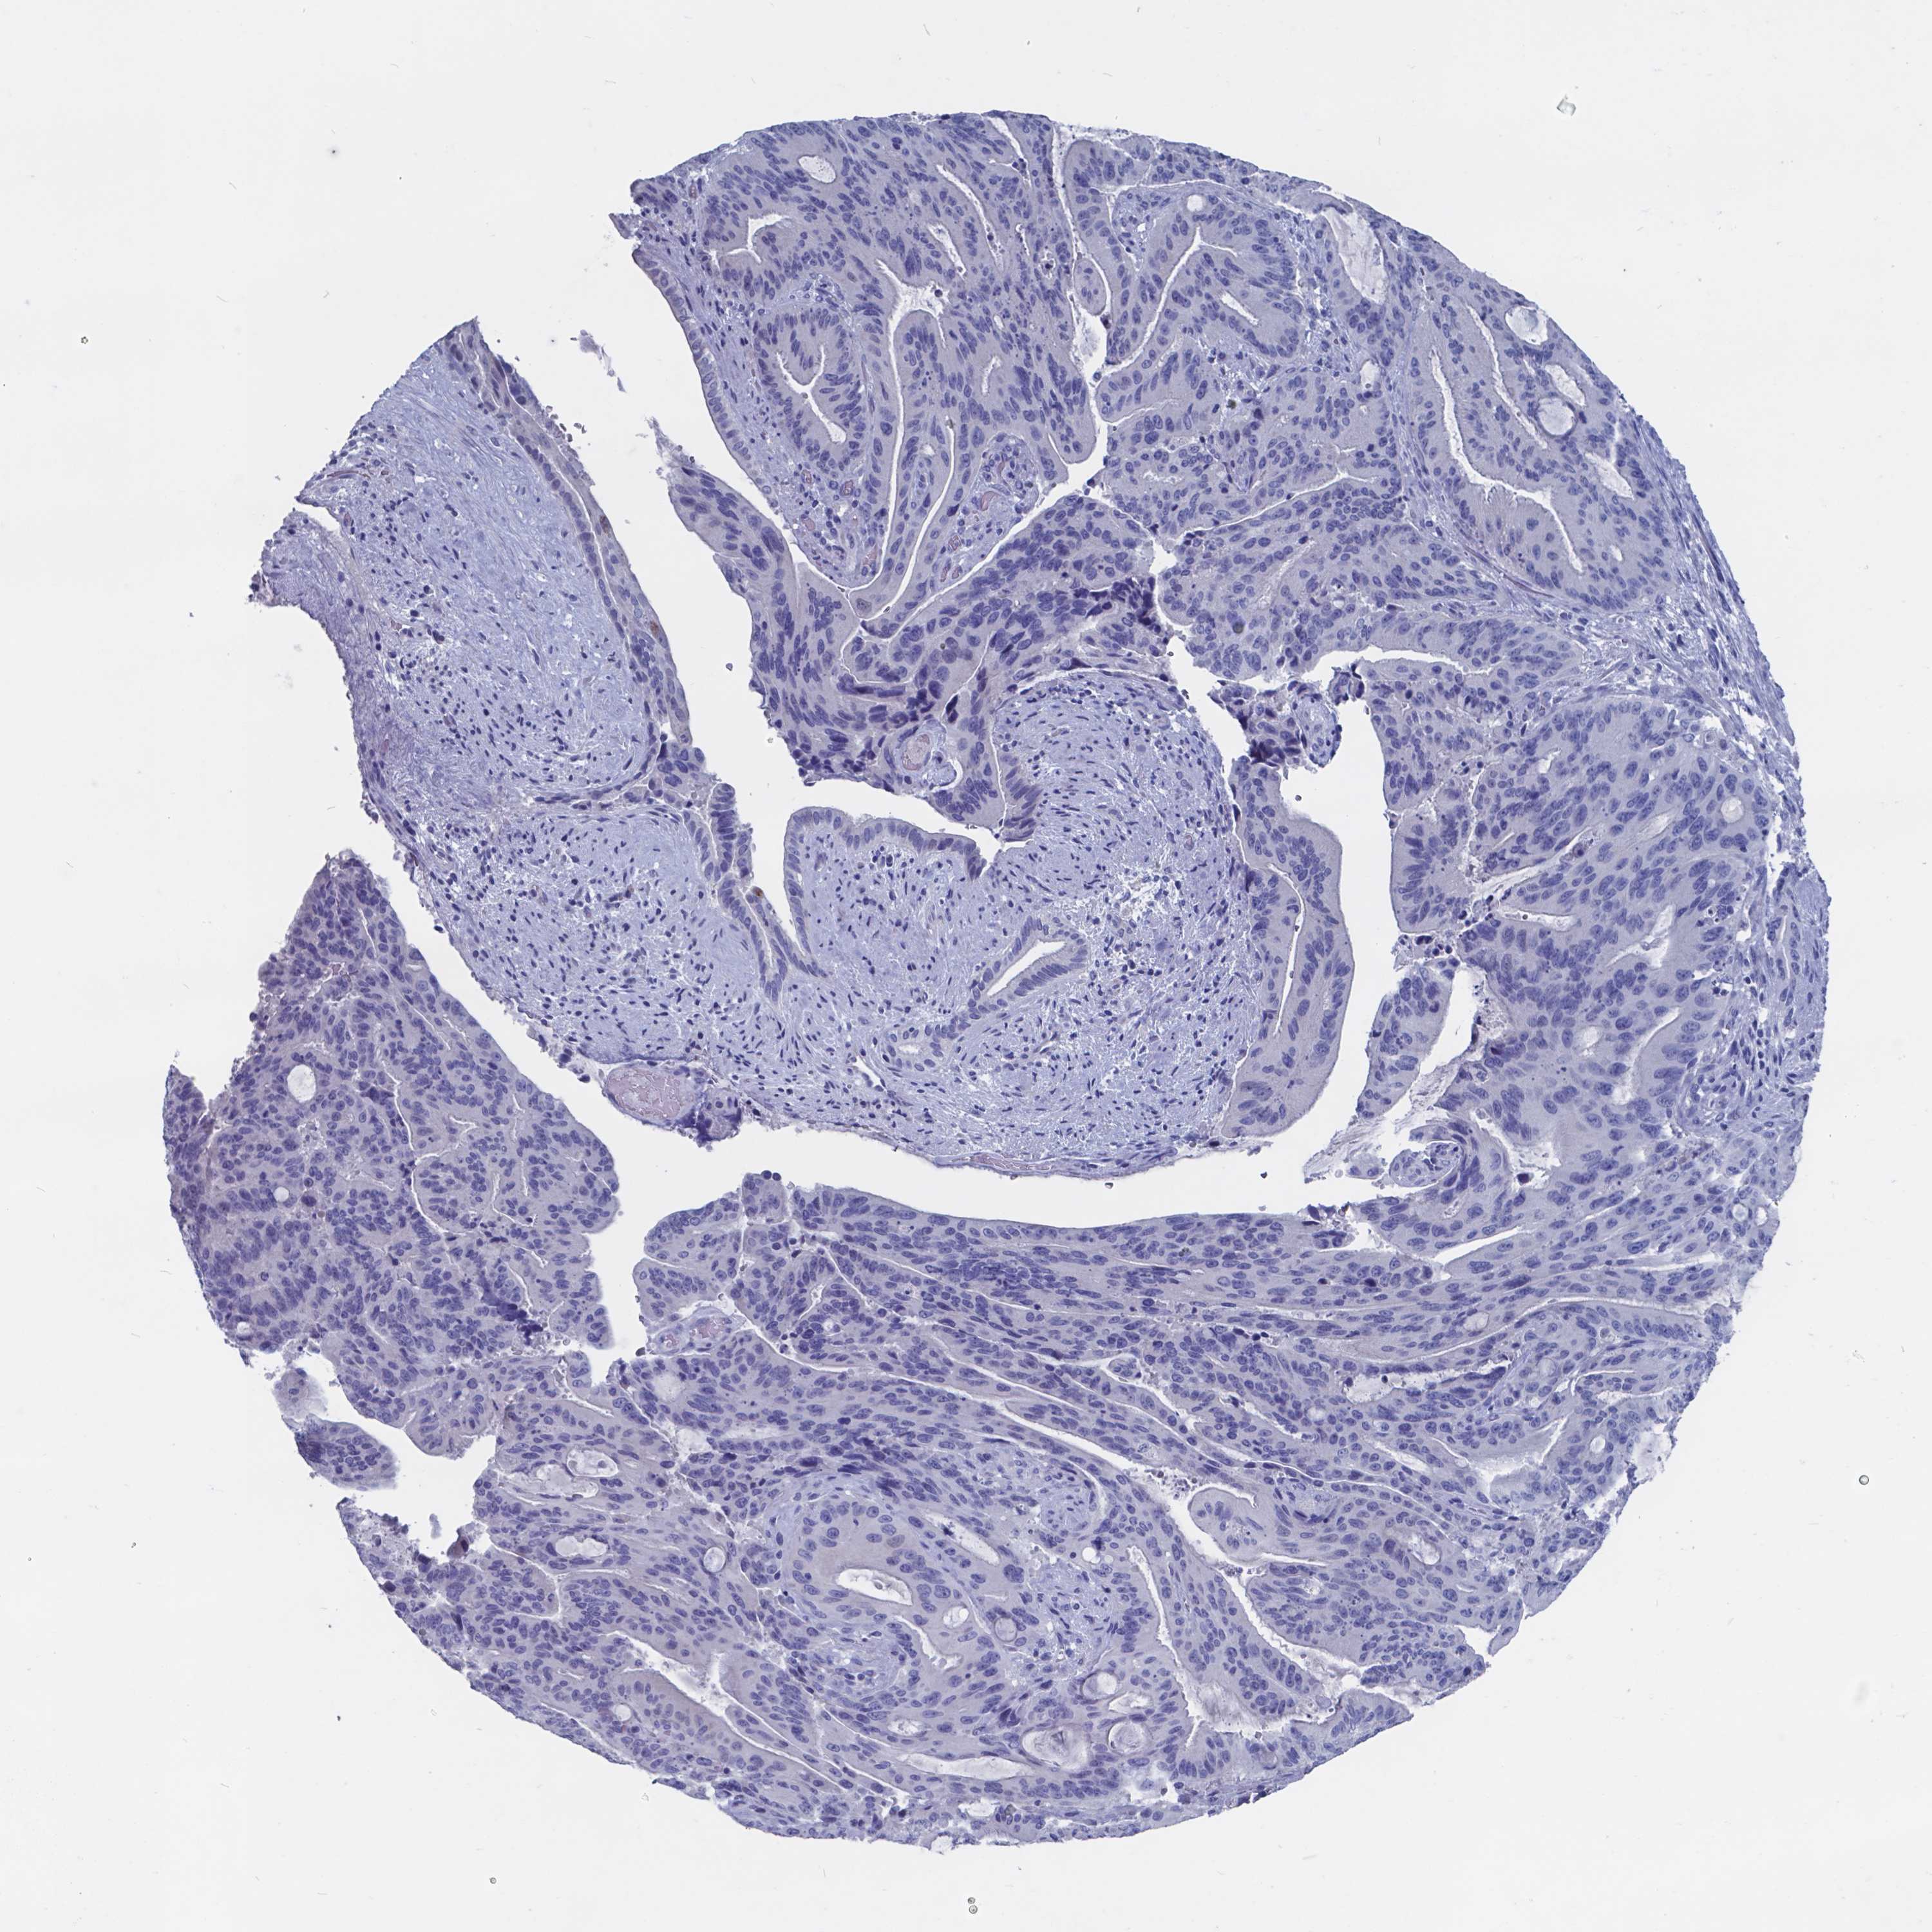

LIVER CANCER - Protein expressioni

A mouse-over function shows sample information and annotation data. Click on an image to view it in a full screen mode. Samples can be filtered based on level of antibody staining by selecting one or several of the following categories: high, medium, low and not detected. The assay and annotation is described here.

Note that samples used for immunohistochemistry by the Human Protein Atlas do not correspond to samples in the TCGA dataset.

Antibody stainingi

Antibody staining in the annotated cell types in the current human tissue is reported as not detected, low, medium, or high, based on conventional immunohistochemistry profiling in selected tissues. This score is based on the combination of the staining intensity and fraction of stained cells.

Each image is clickable and will lead to virtual microscopy that enables deeper exploration of all samples and also displays staining intensity scores, fraction scores and subcellular localization as well as patient and tissue information for each sample.

Antibody HPA002550

Antibody CAB002517

Antibody CAB062567

Antibody CAB073406

Staining

High

Medium

Low

Not detected

Intensity

Strong

Moderate

Weak

Negative

Quantity

>75%

75%-25%

<25%

None

Location

Nuclear

Cytoplasmic/membranous

Cytoplasmic/membranous,nuclear

Carcinoma, Hepatocellular, NOS

Cholangiocarcinoma